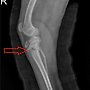

| 슬개골 탈구 4기수술 전 후 회복영상 | 25.03.07 |

| 슬개골 탈구 4기 수술 전후 | 21.01.08 |